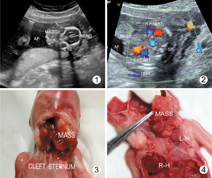

孕妇,28岁。孕2产1,孕16周,否认孕早期毒物接触及病毒感染史,孕早期唐氏筛查低风险,实验室检查未见明显异常。产前超声检查显示:胎儿生长参数正常,胎儿颈部及口腔外可见一个范围约30 mm×26 mm×28 mm的稍高不均匀回声包块(图1),自颈部与口腔缺损处向外突出,包块形态不规则,向下延伸至左侧胸腔上部,包块下方可见一规律搏动的类似心脏结构与之相连(图2),四腔心显示不清。胎儿右侧胸腔亦可见一心脏结构搏动(图2),四腔心显示尚清,显示与大血管相连。系统扫查未见其他明显异常。超声诊断:胎儿胸部、颈部及下颌部实性非均质性包块,考虑为伴心脏结构的胸、颈、口腔寄生胎。

引产后尸体解剖可见:下颌部至胸骨上窝皮肤裂开,下颌骨中断,下颌部可见大小约35 mm×25 mm的包块(图3)向外膨出,包块下部分位于左侧胸腔。包块的胸腔部分内可见一小心脏,右侧胸腔另可见一心脏(图4),稍大于左侧胸腔内心脏,并与大血管相连。其他脏器未见明显异常。口腔、颈部至左侧胸腔包块病检结果:可见三胚层结构,证实为寄生胎。